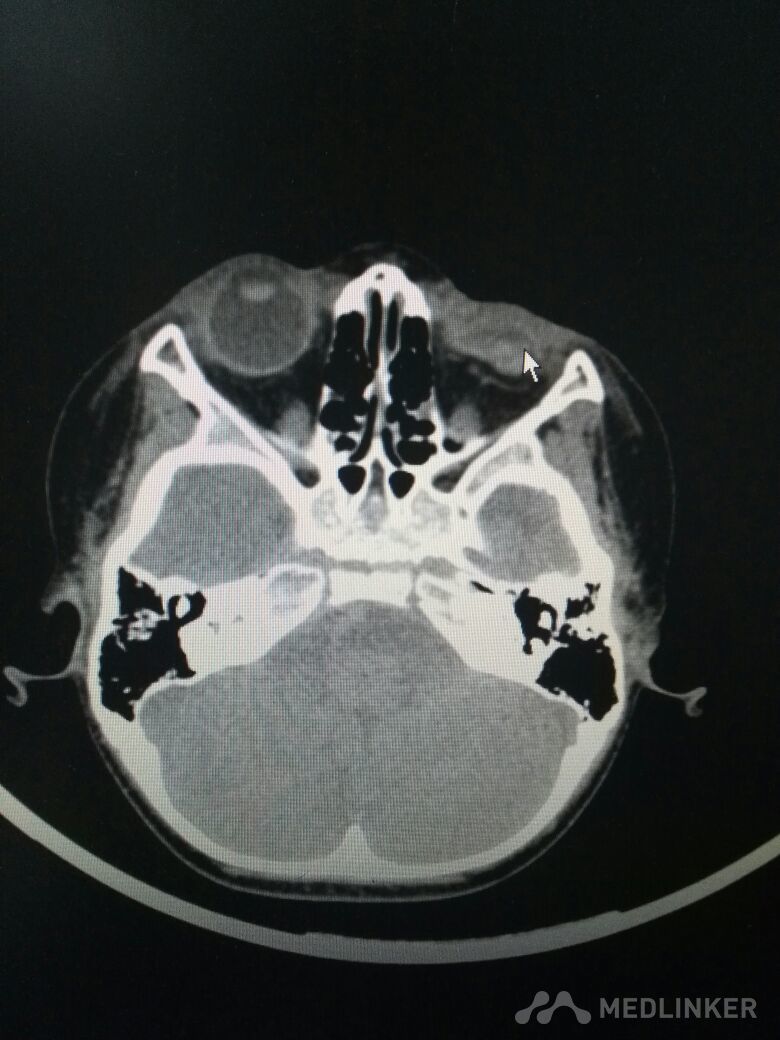

2岁男童,左眼外伤后11小时入院。不慎碰伤左眼,家属说不清是碗碎片还是碰到台阶上。父母在外省打工,奶奶带患儿从农村赶来。 检查不合作,做了急诊CT,左眼球正常形态消失,晶状体未见显示,眼内高密度影(考虑出血)。